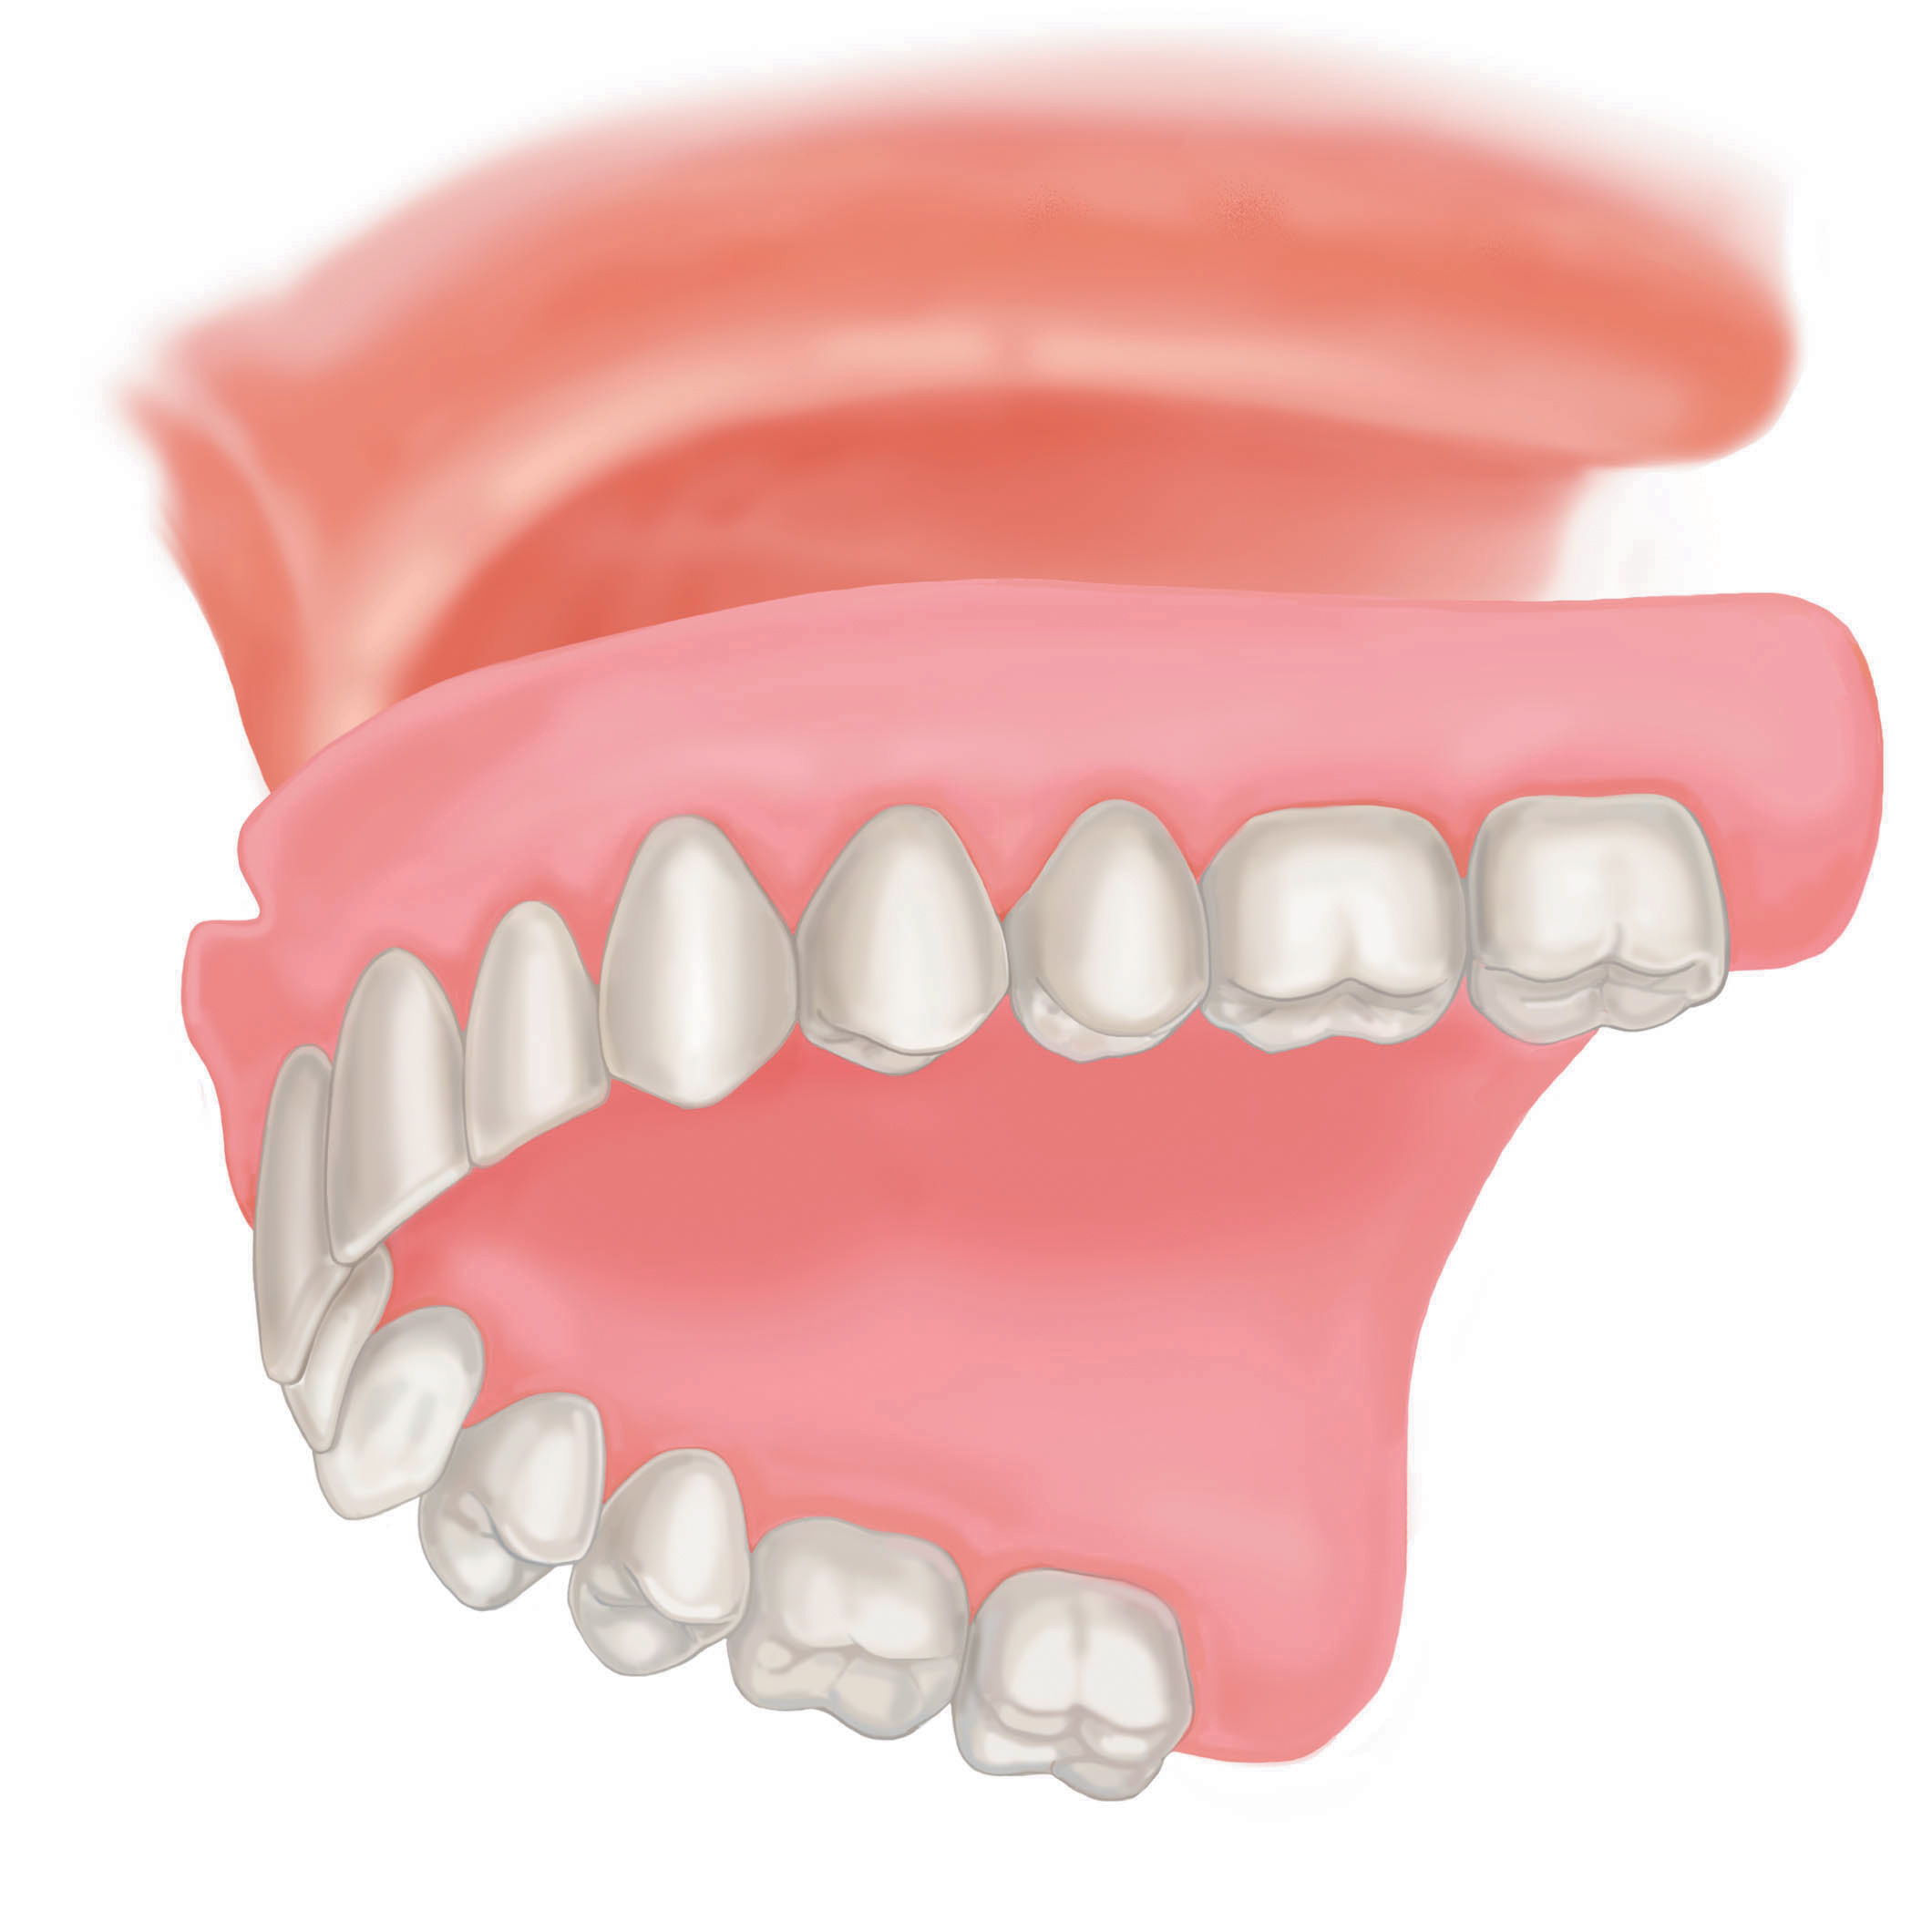

Современные съемные протезы на локаторах: Фото и примеры